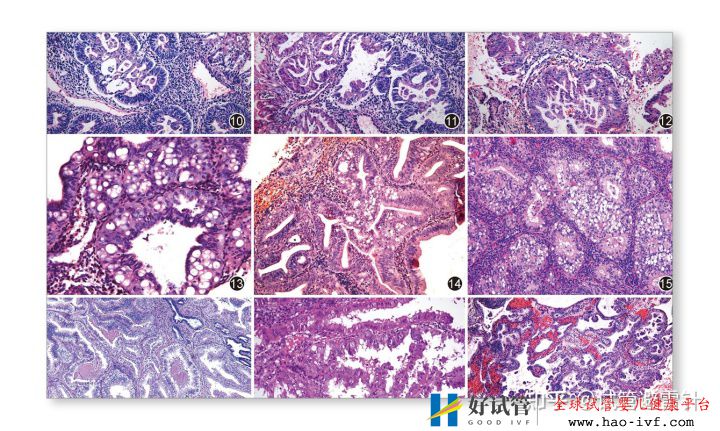

3.女性的子宫内膜异位症

经过药物或手术治疗后仍未怀孕者,具体需要结合子宫内膜异位症的分期情况,进而确定辅助妊娠方式。